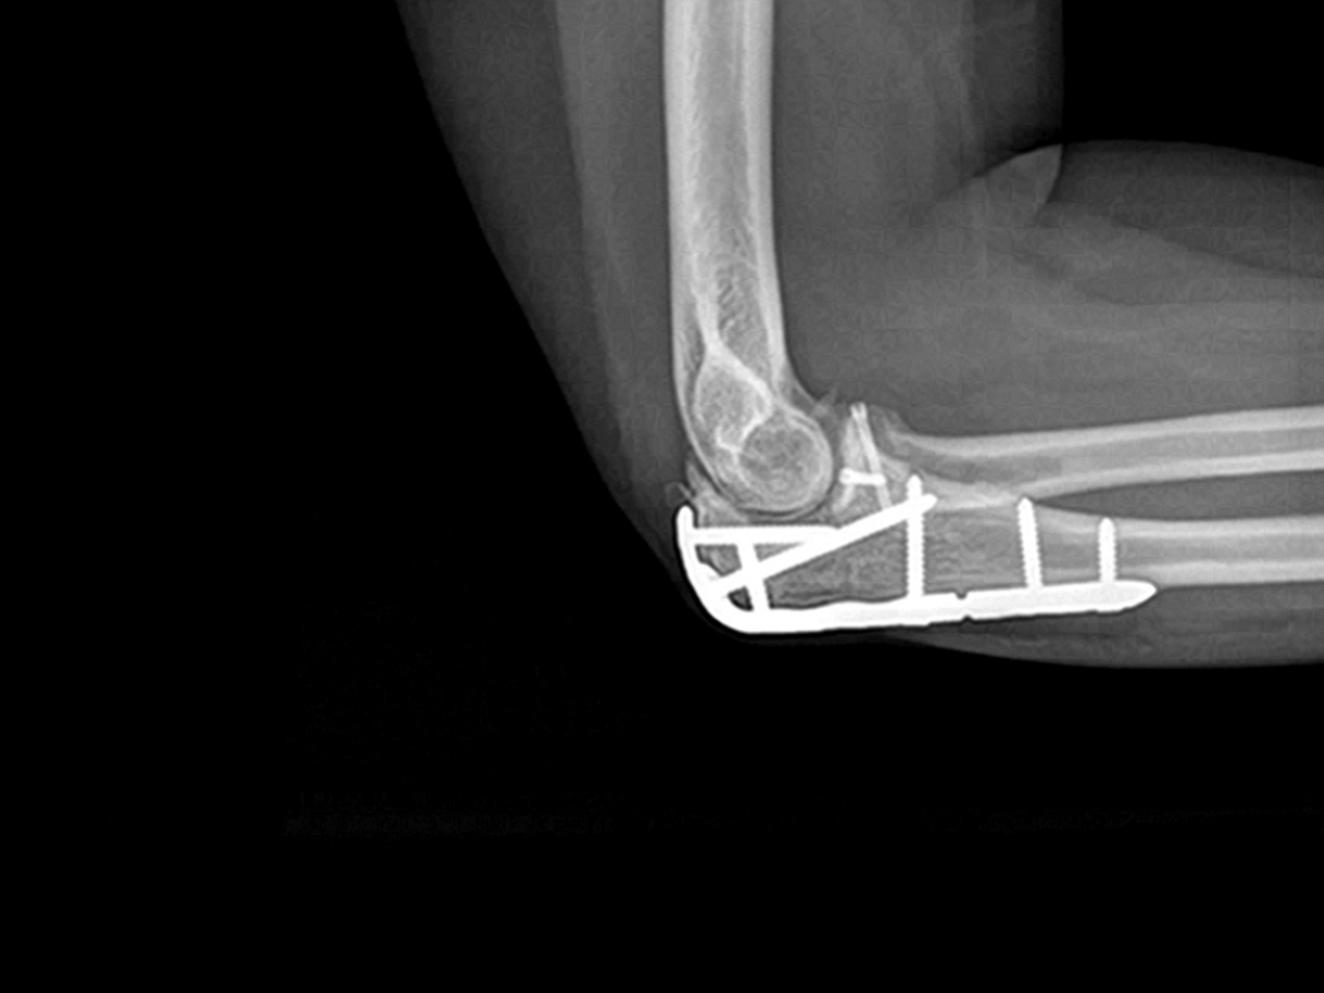

LEPORELLO CLINICAL CASE: COMMINUTED, OPEN OLECRANON FRACTURE WITH CONCOMITANT RADIAL HEAD FRACTURE

We present a case of a comminuted, open fracture of the olecranon (AO 2U1C) with a concomitant fracture of the radial head (AO 2R1C).